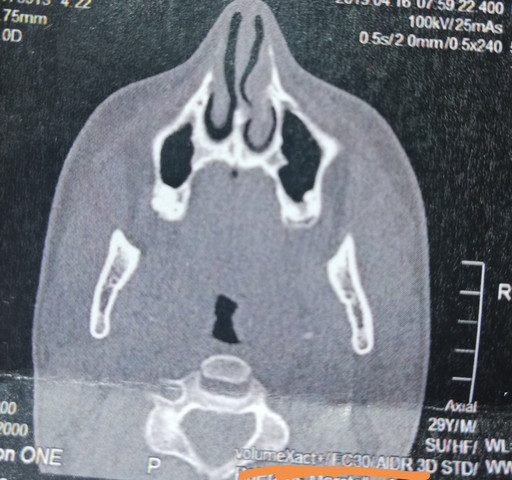

CT der Nasennebenhöhlen /Nase, alles ok? (kernspintomographie)

Source: www.gesundheitsfrage.net